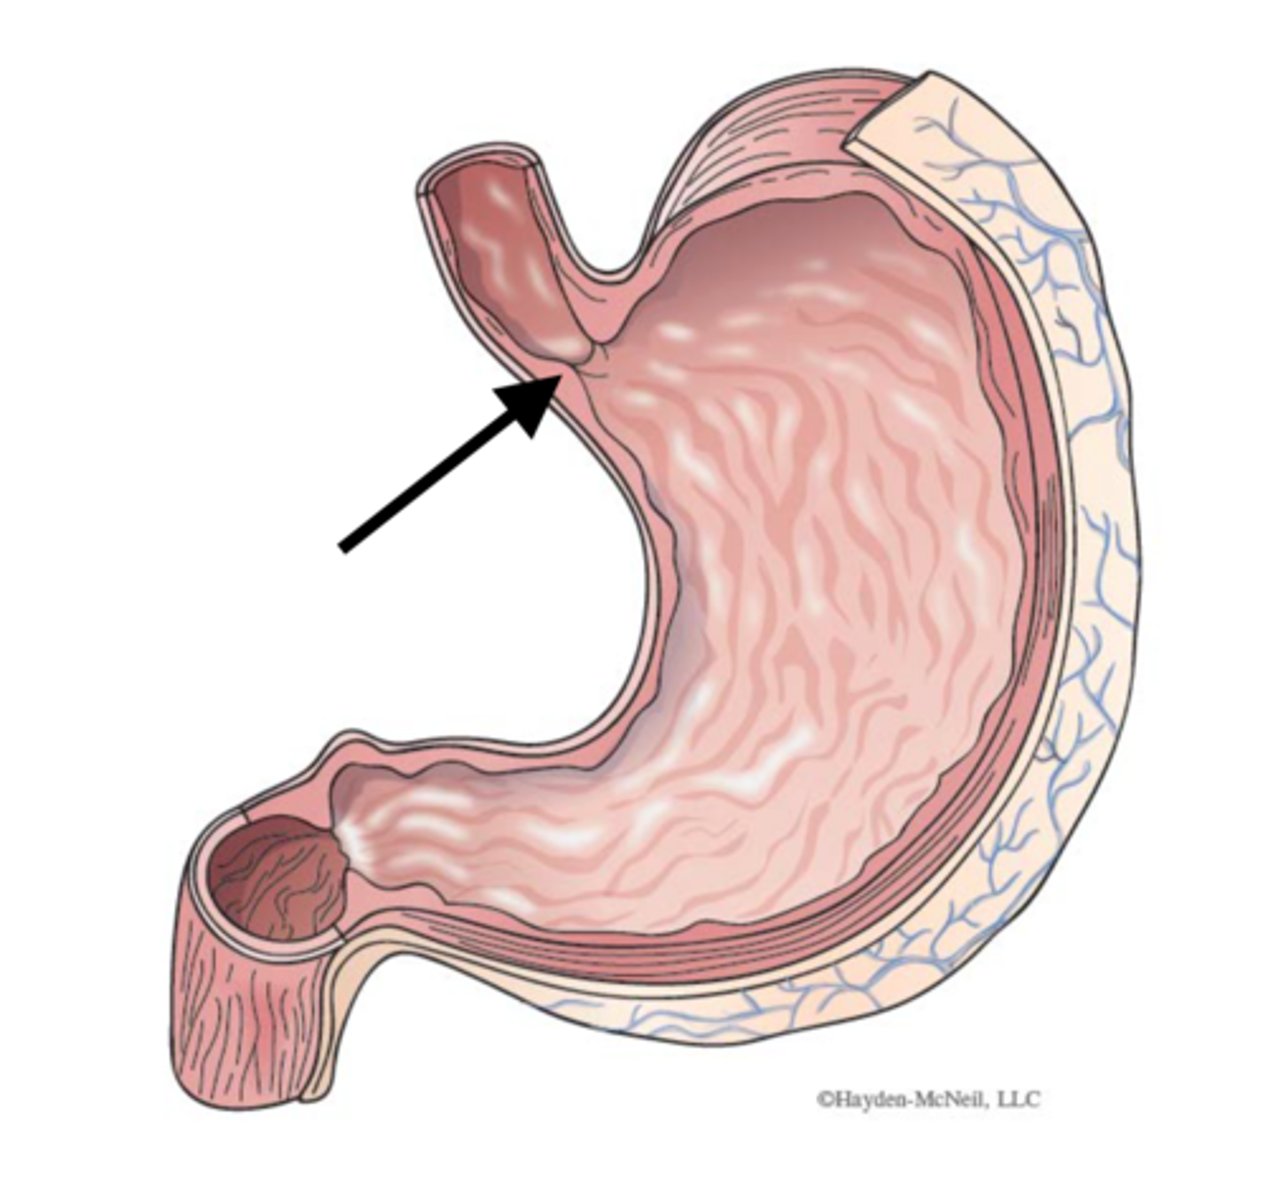

stomach

cardia

fundus (stomach)

body (stomach)

pylorus

pyloric sphincter

cardiac sphincter (lower esophageal sphincter)

esophageal hiatus